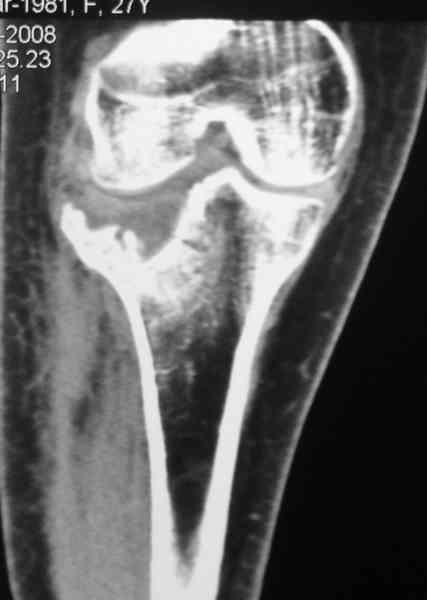

[Ortho] Застарелый перелом 41С3

Уважаемый Абдурашид. Если нет противопоказаний , то из оперативных

способов, я бы рекомендовал следующие: Полное замещение наружного

мыщелка аллотрансплантатом либо открытая репозиция с элевацией и

замещение дефекта ауто или аллокостью. В Ваших условиях , я бы

рекомендовал второй способ. Во-время элевации необходимо разъединить

фрагменты со стороны сустава ( надсечь скальпелем по линиям перелома,

а затем тонким остеотомом их разъединить. При помощи долота произвести

неполную остеотомию ( захватите не менее 1,5 - 2 см губчатой кости и

поднять фрагменты, визуально отрепонировать и фиксировать 2-3 спицами.

Дефект заместить костным ауто или аллотрансплантатом. Окончательная

стабилизация пластиной ( лучше с угловой стабильностью, либо АВФ -

позволит спокойно устранить угловую деформацию.

Недавно поступила больная через 1,5- 2 месяца.